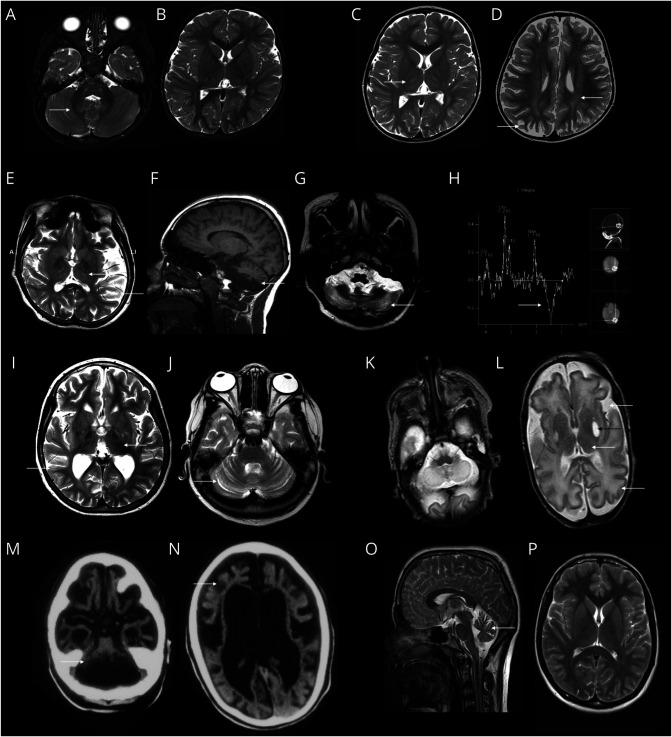

Clinical Features, Biochemistry, Imaging, and Treatment Response in a Single-Center Cohort With Coenzyme Q Biosynthesis Disorders.

Disorders of coenzyme Q (CoQ) biosynthesis comprise a group of 11 clinically and genetically heterogeneous rare primary mitochondrial diseases. We sought to delineate clinical, biochemical, and neuroimaging features of these disorders, together with outcomes after oral CoQ supplementation and the utility of peripheral blood mononuclear cell (PBMNC) CoQ levels in monitoring therapy.

This was a retrospective cohort study, registered as an audit at a specialist pediatric hospital (Registration Number: 3318) of 14 patients with genetically confirmed CoQ biosynthesis deficiency, including 13 previously unreported cases.

We show that oral doses of CoQ up to 70 mg/kg/d were needed to ameliorate neurologic features. Additional idebenone was required to control seizures in some cases, and 3 children with neonatal-onset neurologic disease died in early childhood despite receiving high-dose oral CoQ from birth. We also demonstrate that early diagnosis and treatment of CoQ deficiency with oral supplementation (30 mg/kg/d) can reverse renal manifestations and can completely prevent kidney disease over 10 years of follow-up. PBMNC CoQ levels increased after oral CoQ supplementation, demonstrating absorption of exogenous CoQ into the bloodstream.

An early genome-wide diagnostic approach is needed for expeditious diagnosis of CoQ biosynthesis disorder because our study demonstrates that there are no pathognomonic blood, muscle, or imaging biomarkers of these diseases. Our findings indicate that earlier diagnosis and treatment with high-dose CoQ is key in halting progression of kidney disease or preventing it altogether. This study uses serial PBMNC CoQ levels to monitor therapy. Patients with genetically confirmed CoQ biosynthesis disorder should receive high-dose oral CoQ as soon as possible after presentation, regardless of genetic cause, to prevent disease progression, but parents of children with neonatal or infantile neurologic presentations should be counseled about the poor prognosis.